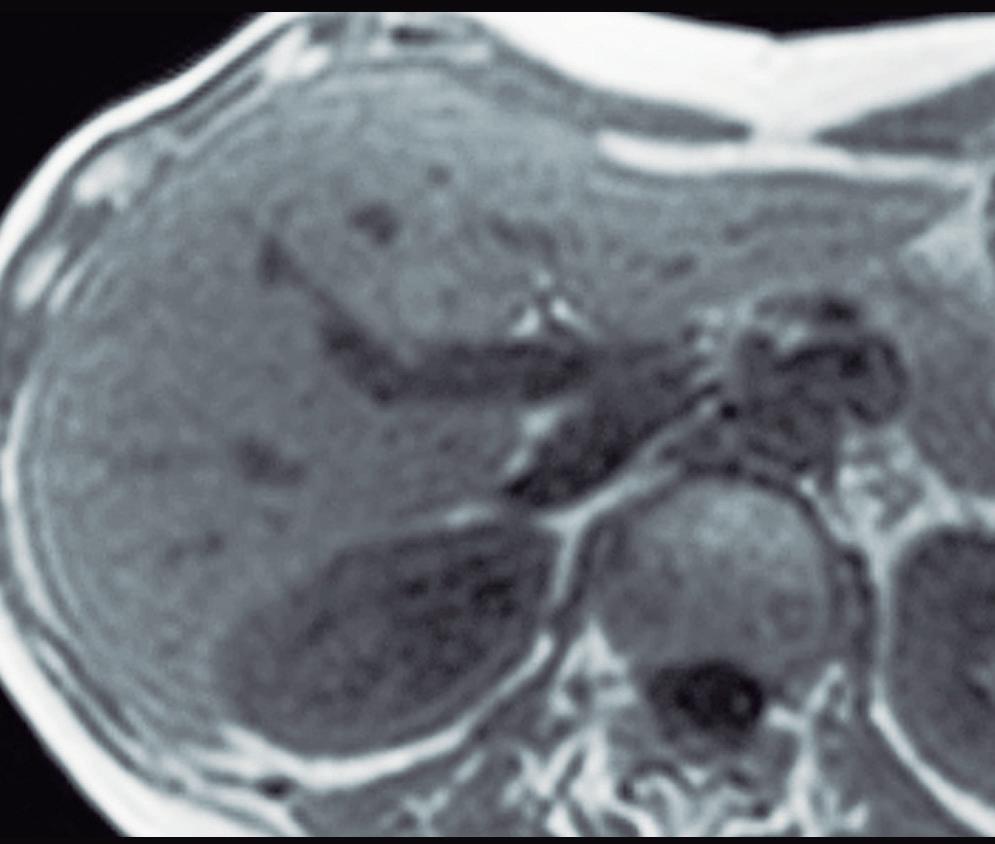

con dolor o molestias. Se piensa que es una respuesta hiperplásica a una malformación arterial preexistente y está formada por hepatocitos normales, células de Kupffer, escasos ductos biliares pequeños y arteriolas prominentes. Las lesiones similares a la HNF también suelen observarse en pacientes con trastornos vasculares tales como síndrome de Budd Chiari e hiperplasia nodular regenerativa. También se han descripto en pacientes con cáncer que han sido expuestos a derivados del platino.3 El tamaño de las lesiones varía de milímetros hasta al menos 10 cm. Típicamente, la HNF presenta una cicatriz central y es irrigada mediante una arteria desde el centro en forma centrífuga; esta una característica bastante específica ya que, tanto las lesiones hepáticas benignas como malignas, son nutridas desde la periferia mediante las ramas de la arteria hepática. Debido a su histología, la textura es similar a la del parénquima normal y por eso su detección puede ser difícil, en particular en las imágenes sin contraste endovenoso y si el nódulo es pequeño.

La HNF se manifiesta como uno o más nódulos (múltiple en aproximadamente 20%) de bordes netos y contornos lobulados. En la TCMC tiene densidad similar o apenas menor a la del parénquima adyacente. Si la cicatriz es visible (60%) en la TC es hipodensa. (Figura 3) En la RM su señal es isointensa o apenas hipo o hiperintensa en T1 e isointensa o un tanto hiperintensa en T2. (Figura 4) La cicatriz es hiperintensa en T2 (visible 80% en la RM), característica clave para diferen-

ciarla del hepatocarcinoma fibrolamelar (cuya cicatriz es hipointensa en T2 por fibrosis o por calcificación). Por otra parte, en algunos casos la diferenciación puede ser difícil ya que ambas son lesiones que ocurren en pacientes jóvenes con hígado sano y presentan similar aspecto y comportamiento poscontraste. Típicamente, la lesión realza intensamente en la fase arterial en forma homogénea y su densidad (o intensidad de señal en la RM) disminuye en fases sucesivas pero suele persistir levemente reforzada con respecto al hígado.4, 5 Los hepatocitos que forman la HNF son positivos para las proteínas transportadoras, característica que, sumada a la presencia de conductos biliares, explican el refuerzo de estas lesiones en la fase hepatobiliar en la RM con empleo de contraste hepatoespecífico. Esto permite establecer el diagnostico con un alto grado de certeza y alejar (sin descartar absolutamente) la posibilidad de un adenoma hepatocelular. El refuerzo puede ser isointenso con el parénquima, difusamente hiperintenso e hiperintenso en la periferia. (Figura 5) Dada la naturaleza benigna de la lesión, carece de riesgo de malignidad y el manejo de la HNF es conservador.8 Si el diagnóstico por imágenes es firme, no se requiere seguimiento. Si la lesión es sintomática, presenta características no típicas, es pediculada o exofítica, el caso debería ser sometido a discusión por un equipo multidisciplinario. La indicación de cirugía por la HNF es excepcional en casos sintomáticos o en raras circunstancias como sangrado o rotura.

Figura 3. HNF en la tomografía computada A: Imagen en plano coronal de tomografía computada en fase arterial con reconstrucción MIP (máxima intensidad de proyección), demuestra una lesión sólida exofítica en el sector caudal del segmento IVb. Tiene bordes netos y contornos algo lobulados y exhibe hiper refuerzo en fase arterial. En el centro se aprecia una zona de menor densidad que sugiere una cicatriz. También nótese una pequeña imagen de similar aspecto ubicada en el segmento V. B: Imagen en plano coronal en la fase venosa portal que ilustra como la lesión se ha hecho isodensa con el parénquima y es imperceptible. Sólo se sospecha por la deformación del contorno que produce su crecimiento exofítico.

A: En el domo hepático se observa en la secuencia T2 con supresión grasa un nódulo sólido que tiene una señal levemente hiperintensa con respecto al parénquima. Tiene bordes netos. Presenta una cicatriz central de mayor intensidad de señal. B: Imagen en secuencia T1 obtenida en fase arterial que demuestra el hiperrefuerzo de la lesión con excepción de su cicatriz central. C: Imagen en fase portal en la que se puede apreciar que la lesión sólo conserva una leve hiperintensidad con respecto al parénquima. Persiste sin refuerzo la cicatriz central. D: Imagen obtenida en fase de equilibrio. La lesión sólo muestra una hiperintensidad sutil y se puede apreciar el refuerzo tardío de la cicatriz, típico de la HNFl.

Figura 5. HNF en la RM con contraste hepatoespecífico

A: Imagen en plano axial ponderada en secuencia T2 que demuestra una lesión sólida de crecimiento exofítico a partir del sector medial del segmento VI. Tiene bordes netos y una señal ligeramente heterogénea de intensidad similar a la del parénquima. Se observa una pequeña cicatriz excéntrica hiperintensa. B: Imagen en secuencia T1 en el plano axial obtenida en la fase arterial que muestra el hiper refuerzo de la lesión con excepción de la cicatriz. C: Imagen obtenida en la fase hepatobiliar luego de administrar el contraste hepatoespecífico que demuestra el refuerzo difuso de la lesión moderadamente hiperintenso sin realce de la cicatriz. Hallazgos típicos de una HNFl.